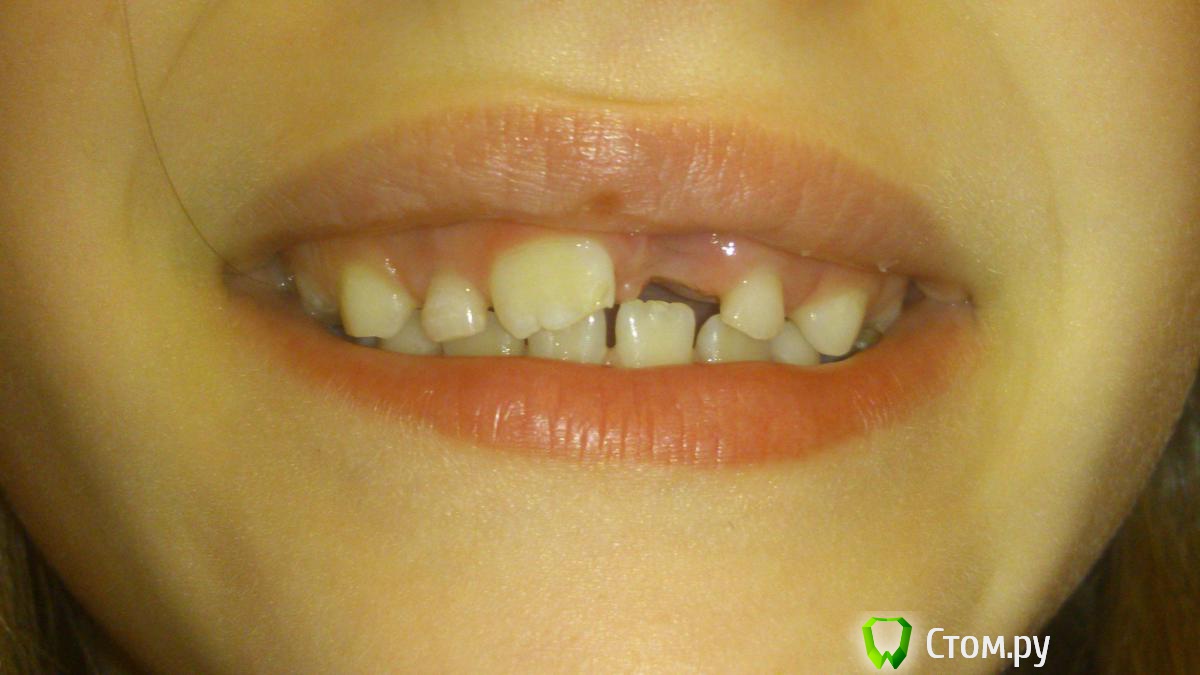

Merilly Опубликовано 25 февраля, 2014 Поделиться Опубликовано 25 февраля, 2014 Добрый день! Дочке 6 лет, в результате травмы удалили верхний постоянный центральный резец. (спасти было нельзя) Может ли нам современная ортодонтия предложить что то еще кроме пластинки? Если нет, не повредит ли пластинка другим зубам? Нужна ли пластинка нам сразу на 2 челюсти? Отличаются ли пластинки по материалам и страной изготовления? Если да то какую пластинку лучше? Какой план лечения Вы нам предложили бы ? (хочется сделать для ребенка все, что бы он не мучился и не стеснялся улыбки). И очень хочется плакать после того как нам в местной поликлинике предложили взрослую пластинку со взрослым протезом зубным , подточив все под наш размер. Спасибо. Ссылка на комментарий

m.d.n Опубликовано 18 марта, 2014 Поделиться Опубликовано 18 марта, 2014 ЛМ активатор - какие показания для 6-летнего ребенка?по этим фото у ребенка 2 класс Ссылка на комментарий

Force Опубликовано 18 марта, 2014 Поделиться Опубликовано 18 марта, 2014 По этим фото у ребенка сменный прикус. Кейс не задокументирован по правилам, если вы хотите назначать лечебный аппарат. Подбор ЛМ-активатора осуществляется врачом на основании ДИАГНОЗА (включая цефалометрию). А по поводу показаний к лечению дистального прикуса (неподтвержденного и неочевидного), существуют разные мнения. Скорее всего, в данном случае в данном возрасте их не будет. Я это все к тому, что не стоит так швыряться назначениями. Ссылка на комментарий